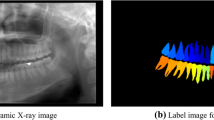

X-ray images are essential data sources for checking the condition of the teeth, gums, jaws, and bone structure of the mouth. Tooth recognition is fundamental in image-processing-based diagnoses. In most previous recognition studies, only four-axis-based object-detection models have been considered because they perform normal object detection while the object is resting on a flat surface. However, because the teeth have various orientations, the existing four-axis-based model leads to inaccurate and inefficient recognition results. Thus, in this study, we propose a five-axis-based object-detection model that considers the orientation of the tooth. Based on a tooth-image dataset labeled using the five-axis ground truth, our proposed method processed five-axis annotated data by employing a variant of the faster region-based convolutional neural network. In the experiment, our proposed method outperformed the existing four-axis approach, both qualitatively and quantitatively. The experimental results indicated that the proposed five-axis-based recognition model will be an important basis for a dental-image-based diagnosis.